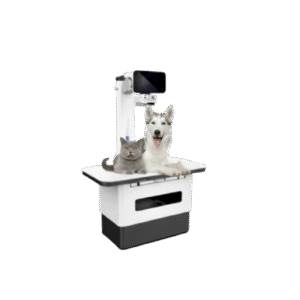

Vetoo DX-VA03 Veterinary Portable Handheld Digital X-Ray Machine

The Vetoo DX-VA03 Veterinary Portable Handheld Digital X-Ray Machine delivers high-quality radiography imaging for animals in clinics, hospitals, and field services. Lightweight, fast, and battery-powered, it provides accurate diagnostic results anywhere. Best digital handheld X-Ray machine at a low price in Bangladesh with special discount and savings offers.

Introducing the Vetoo DX-VA03 Veterinary Portable Handheld Digital X-Ray Machine, a powerful, modern, and ultra-compact imaging tool designed for veterinary diagnostic excellence. This advanced portable X-Ray device is ideal for pet clinics, veterinary hospitals, livestock farms, and field researchers. With its lightweight design and high-resolution image output, it ensures quick diagnosis and better clinical decision-making. If you are looking for a portable veterinary X-Ray system at the best price in Bangladesh, the Vetoo DX-VA03 stands as an outstanding solution.

Designed for busy veterinary professionals, the DX-VA03 handheld X-Ray offers fast exposure times, smart control settings, and stable radiation output. Whether you diagnose small animals such as dogs, cats, birds, rabbits, or large livestock like cows, goats, sheep, and horses, this machine delivers reliability every time. It is not only easy to carry but also easy to use in tight spaces, remote farms, and emergency field operations.

The Vetoo DX-VA03 features advanced digital imaging technology. With adjustable exposure settings, controlled radiation output, and optimized battery performance, users get superior diagnostic results. The handheld device works seamlessly with digital DR imaging systems and smart detectors. This makes the machine a smart choice for modern veterinary practices looking for advanced technology at the best price in Bangladesh.